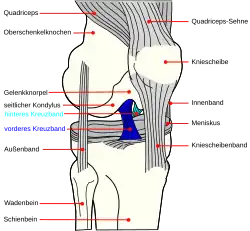

Von einem Kreuzbandriss oder einer Kreuzbandruptur spricht man bei einem unvollständigen (partiellen) oder vollständigen (kompletten) Riss (Ruptur) eines oder beider Kreuzbänder. In den meisten Fällen ist das vordere Kreuzband (Ligamentum cruciatum anterius) betroffen. Durch Überschreiten seiner Reißfestigkeit kommt es zu Einriss oder Abriss des Bandes, eventuell mit Ausriss des knöchernen Ansatzes (Insertion).

In den wenigsten Fällen sind Kreuzbandrisse isolierte Verletzungen. Die Rupturen werden meist von anderen Läsionen weiterer Bänder und der Menisken begleitet.[1] Es können zwei Arten von Kreuzbandrissen unterschieden werden:

- Vorderer oder hinterer Kreuzbandriss mit sagittaler, das heißt von vorne nach hinten verlaufender, Instabilität und positivem Schubladenphänomen und positivem Lachmantest

- Kombinationsverletzung mit Schubladenphänomen in Drehstellung des Fußes nach innen oder außen:[2]

- Anteromediale Rotationsinstabilität (AMRI, vorne-mittige Drehbewegungsinstabilität): vorderer Kreuzbandriss, Riss des Innenmeniskus und der mediodorsalen Kapsel, oft zusätzlich (meist zur Mitte zeigender) Riss des Innenbandes (sogenannte Unhappy Triad).[3]

- Anterolaterale Rotationsinstabilität (ALRI, vorne-seitliche Drehbewegungsinstabilität): Riss des hinteren Kreuzbandes, des Außenbandes und der dorsolateralen Kapsel.[4]

- Posterolaterale Rotationsinstabilität (PLRI, hintere-seitliche Drehbewegungsinstabilität): Riss des Außenbandes und des hinteren Kreuzbandes bei hinterer-mittiger, beziehungsweise hinterer-seitlicher Drehbewegungsinstabilität.[5]